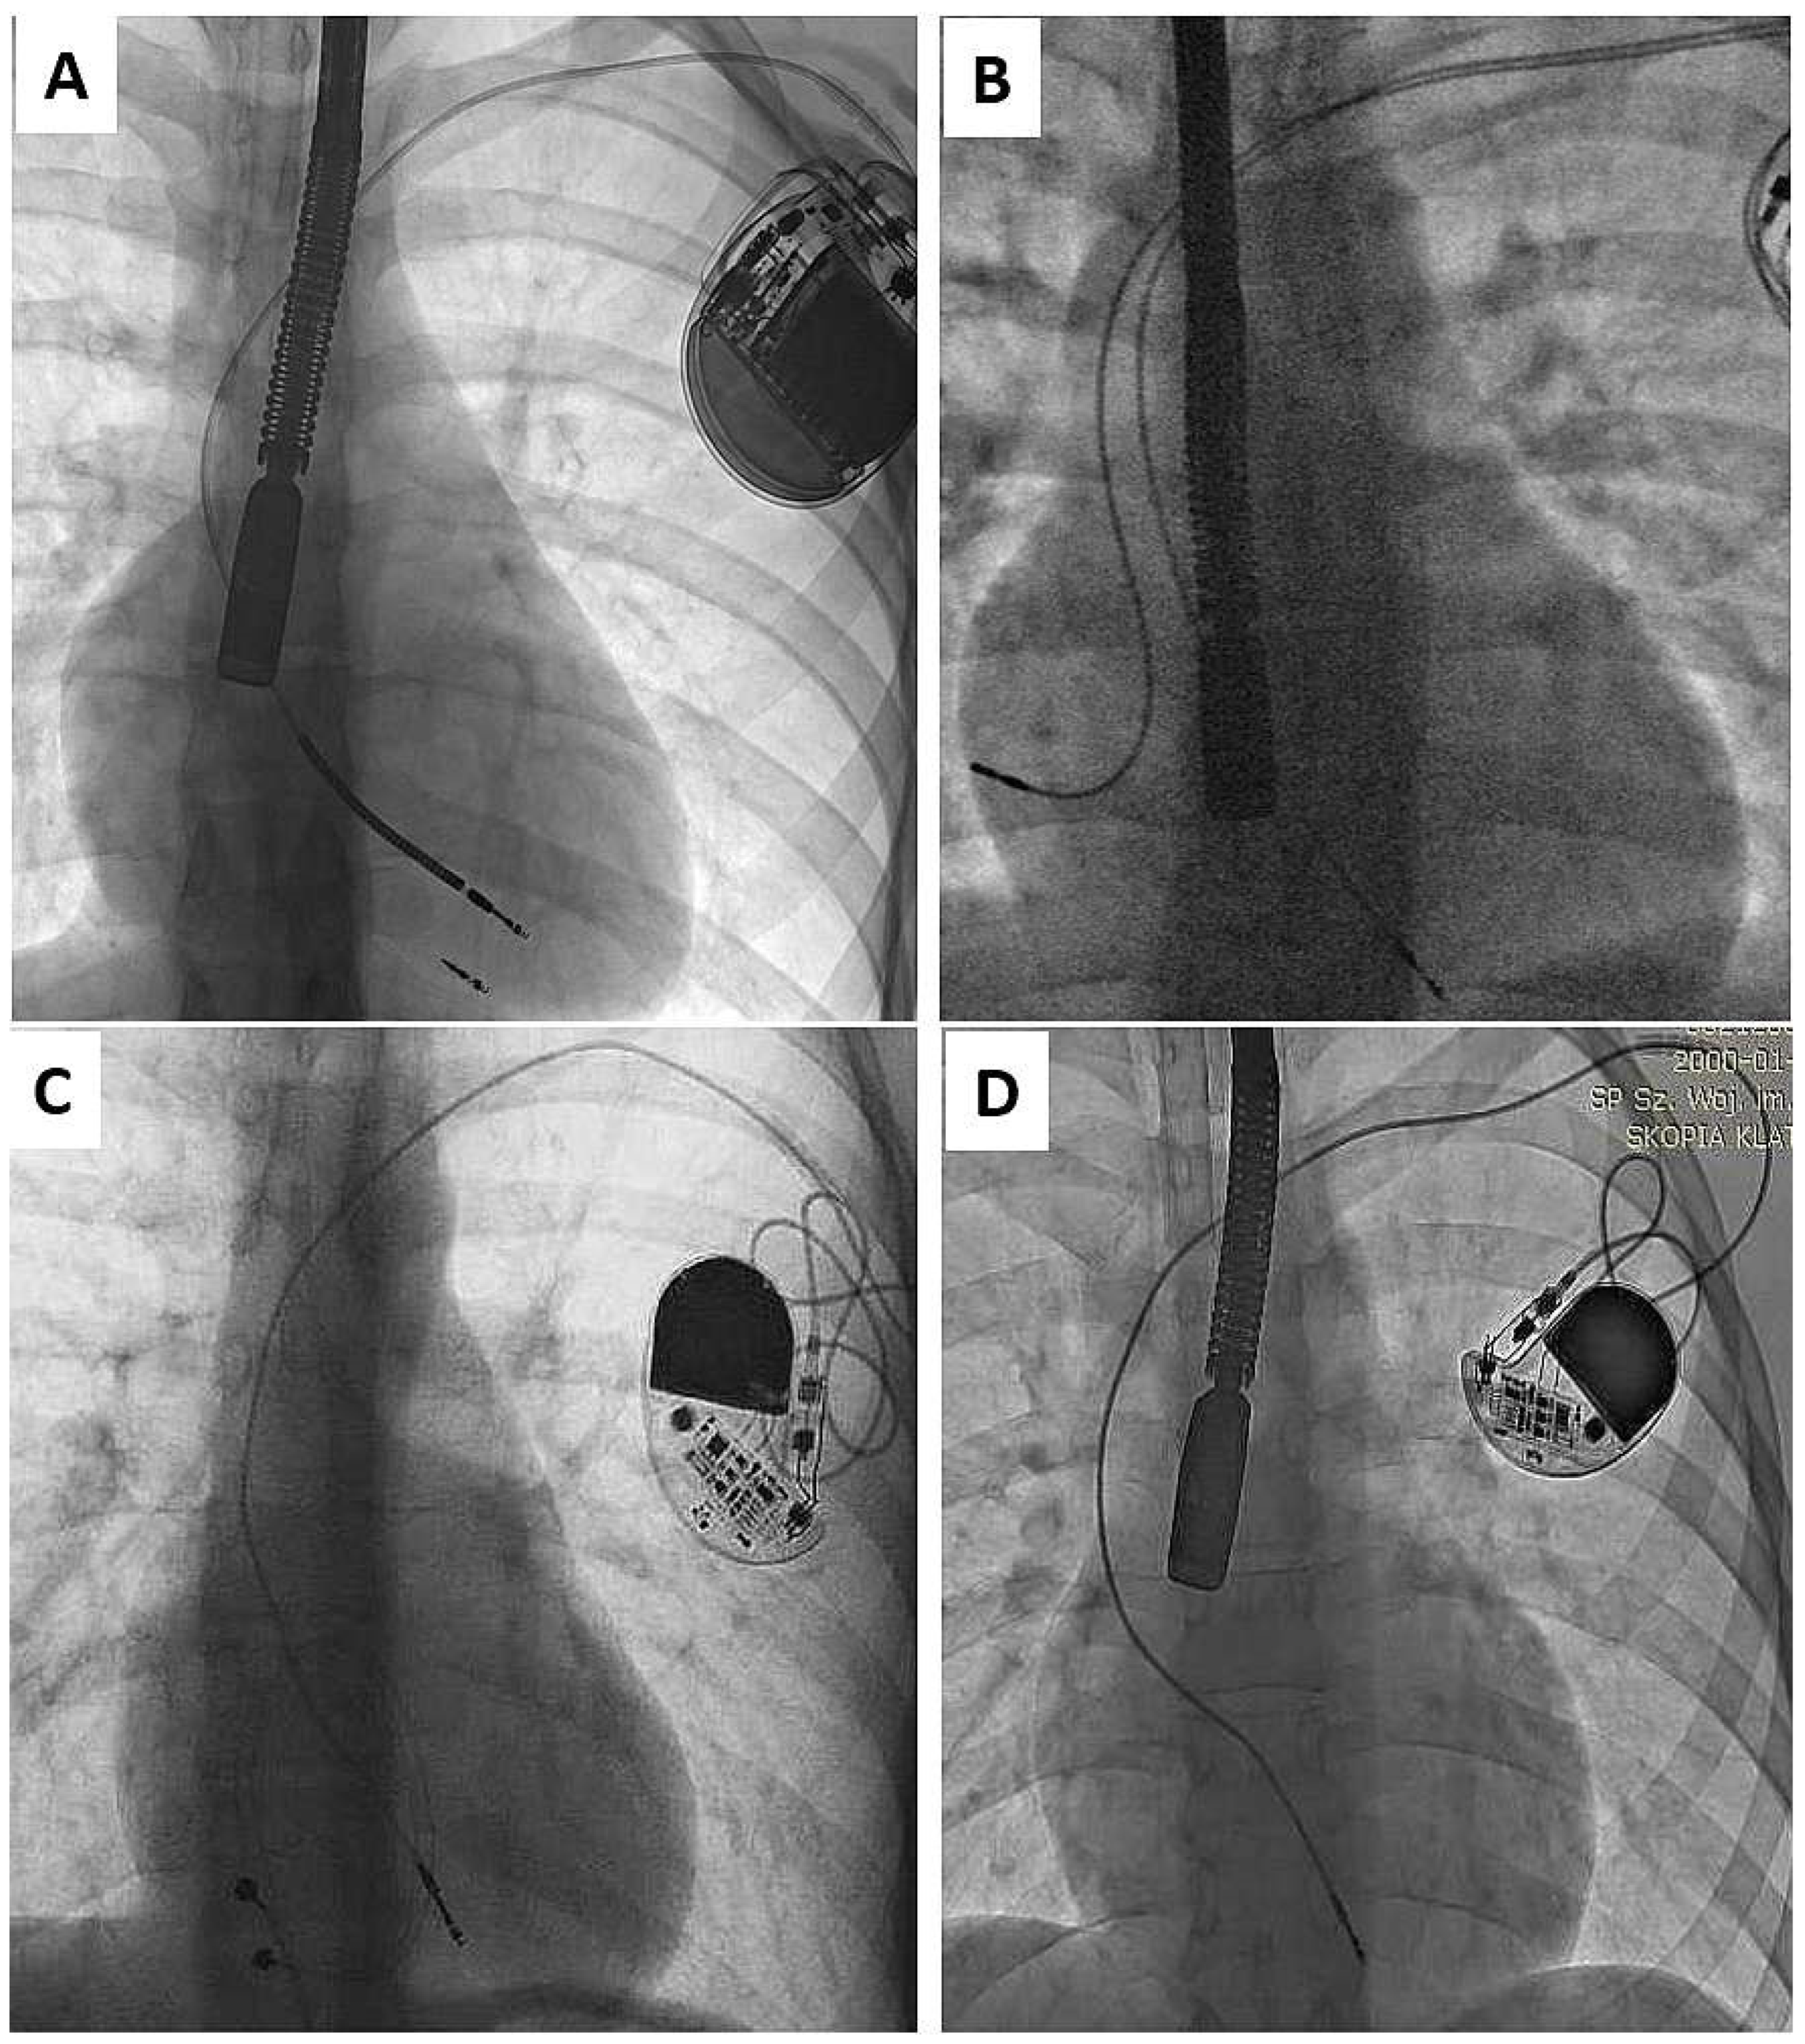

As mentioned in the Introduction Section, the problem appears when children enter adulthood with old or very old leads, if still “functional”. Adequate pacing/sensing thresholds and normal impedance levels do not guarantee long lead function in the context of body growth [3,4,5,6,7,8,33]. Such functional leads, straightened (Figure 1) or looped (Figure 2), can adhere to the heart structures [34]. The leads are covered with a thick film of fibrous, usually calcified tissue, causing additional damage to external lead insulation (by pulling out and moving through the calcified scar). Limited lead longevity, especially in children and young patients [3,4,5,6,7,8,11,12,13,14,15,16,17,18,19] creates the need for lead replacement or new lead implantation with abandonment of non-functional leads [5,11,12,13].

Figure 1.

Straightening of the leads due to body growth (A–D). The unnatural course of the electrode is a common phenomenon in the analyzed population of patients. Adherence of the lead to the vein and heart structures induces scar formation and makes it difficult to extract the lead. Epicardial lead remnants (C) and endocardial led remnants (after previous TLE) (A) are frequent findings in patients with leads implanted in childhood. (B) strained RV lead, during unit replacement atrial lead in atypical tip position was added (D) straightening of the leads, no other pathology is seen.